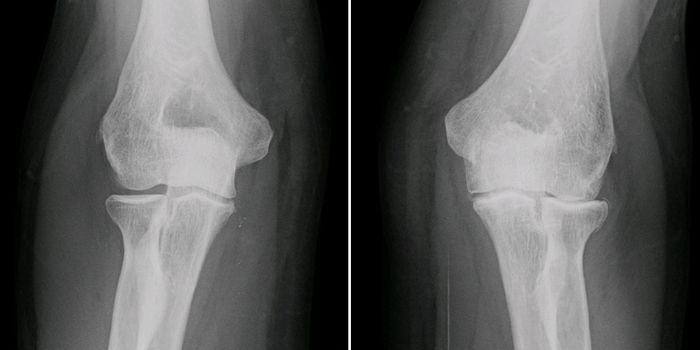

JUN 19, 2018Clinical & Molecular DXThere is a new way to diagnose arthritis and watch its progression slowly over time to determine the best route of treat ...

APR 30, 2024Clinical & Molecular DXIn osteoarthritis, the tissues that cushion joints begin to degenerate, leading to stiffness, pain, and swelling. Accord ...